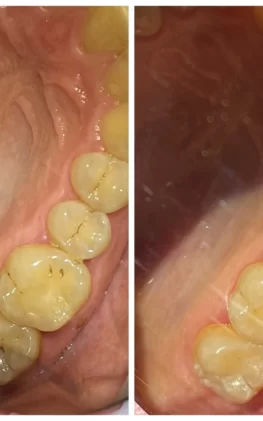

Примеры моих работ